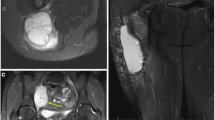

When indicated, MR imaging is the most useful technique for identifying suspected local recurrence or residual disease after incomplete resection [34, 49]. An MR using a T2-weighted sequence with frequency-selective fat saturation or short tau inversion recovery (STIR) or Dixon sequence with water reconstruction is considered to be the most useful first step for detecting recurrent tumor (Fig. 26.3). The morphology of the lesion and the signal intensity contribute to the definition of its character. Low signal intensity on T2-weighted images or diffuse high signal intensity on T2-weighted images excludes tumor recurrence in 99 % of patients. Mature scar tissue usually exhibits low signal intensity (Fig. 26.4) because of its fibrous tissue content, as described in previous studies. Diffuse high signal intensity with a feather-like appearance, without mass effect, generally represents post-therapy change or inflammation. High signal intensity mass-like lesions on T2-weighted images require further examination with intravenous Gd-chelates [50].

Fat-suppressed T1-weighted fast spin echo sequences after Gd-chelate injection can be used to distinguish non-enhancing post-therapy hygroma, seroma, or hematoma from enhancing tumor recurrence, post-therapy fibrosis, granulation tissue, or inflammatory masses (Fig. 26.5). The T1 fat-suppressed images obtained after administration of the contrast agent should be compared to subtraction images (for instance, obtained in the dynamic sequence, see below) or to pre-contrast T1 fat-suppressed images to correct for pseudo-enhancement caused by scaling effects. Absence of contrast enhancement excludes recurrent tumor. On these standard contrast-enhanced images, the differentiation between recurrent viable tumor and post-therapy fibrosis or inflammatory pseudomasses may remain difficult. However, in these cases dynamic contrast-enhanced MR imaging may prove helpful [34, 51]. Dynamic contrast-enhanced MR imaging allows differentiation between inflammation and recurrent or residual tumor. After a rapid bolus injection of contrast, viable tumor exhibits rapid progressive increase of signal intensity followed by washout or plateau phase, whereas the signal from inflammatory changes will also increase but later [52] (Fig. 26.6). The exception is young granulation issue and reactive changes secondary to surgery or radiation within the last 6 months.

Desmoid-type fibromatoses are benign fibroblastic proliferations that arise in the deep soft tissues and are characterized by infiltrative growth in the surrounding soft tissue structures and the absence of a pseudocapsule. Because of this growth pattern, local recurrence after surgery is virtually unavoidable. Routine follow-up MR imaging of patients with desmoid-type fibromatosis seems justified not only to detect (often asymptomatic) local recurrence but also to evaluate the natural behavior of these lesions as they change from cellular active lesions toward mature, collagenous inert lesions [55] (Fig. 26.7).

(a–g) Desmoid-type fibromatosis in the thigh in a 47-year-old male: (a) axial fat-suppressed T1-weighted MR image after gadolinium chelate. The relatively well-defined soft tissue mass shows inhomogeneous enhancement. The non-enhancing area demonstrated low signal intensity on all pulse sequences; (b) 3 months after resection, axial fat-suppressed T1-weighted MR image after gadolinium chelate reveals a postoperative seroma; (c, d) 12 months after resection, axial and coronal fat-suppressed T1-weighted MR image after gadolinium chelate. Spontaneous regression of the postoperative seroma but appearance of new small intramuscular enhancing nodules suggestive of multifocal recurrence (arrow); (e, f) the nodules were identified on ultrasound as hypoechoic soft tissue masses; (g) ultrasound-guided histological Tru-Cut biopsy was performed and recurrence of desmoid-type fibromatosis was confirmed